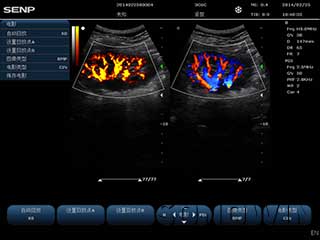

优质图像